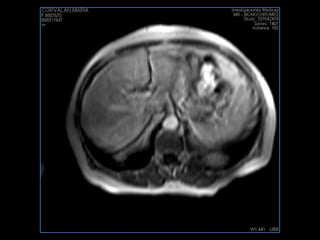

PROTOCOLO hígado graso AXIAL in phase y out phase AX T1 y AX fat sat +SAG T2  CON   GADOLINIO :  COR T1+AX T1(DIN) SAT: NO  FASE: RL THK: 4MM  COIL:  GAP: (FACTOR 1.4)  FOV: 40 CM NEX:2 SINCRONIZACION RESPIRATORIA EN 3 O 4 CICLOS ALE